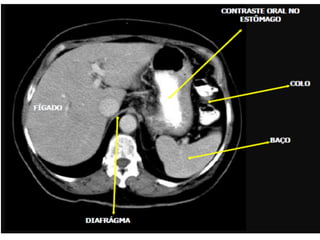

Varredura do abdome total

• Os limites são definidos pelo diafragma até

a sínfise púbica.